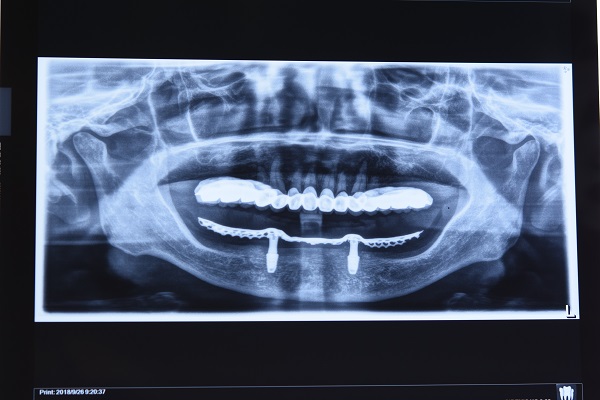

王主任认为:患者上颌半口烤瓷桥从力学原理上说是不良修复体,且较为前突,理应拆除,但患者没有明显疼痛的主诉,牙齿及牙龈皆无不适感,CT片亦未见明显根尖炎症影像,可采用姑息疗法,暂时不拆除。但其上牙过于前凸,与过于萎缩的下颌骨在矢状位极不协调,增大了修复的难度,前牙区覆盖及咬合难以达到最佳。

傅医生仔细阅读了患者的CT片,指出患者下颌骨在垂直向极度萎缩,与下颌神经管很靠近;牙槽骨水平向宽度很窄,若种宽径植体会暴露植体,若种窄径植体则植体本身在咬合力下易折裂。

蔡女士坚持只要有一线希望就不会放弃,她说自己会全力配合医生的治疗方案,也能理解相应的并发症及可能不太佳的修复效果。有了患者的充分信任,王主任和傅医生通力合作,先对患者凹凸不平的牙槽骨进行修整并切除过多增生的松软牙龈,根据口腔修复学原理,在CT指示下,在其下颌双侧尖牙区发现两个仅有的可用种植位点,拟采用目前国内外最为先进的种植修复方式,即种植体支持式Locator球帽固位的下颌半口义齿修复下颌牙列缺失。